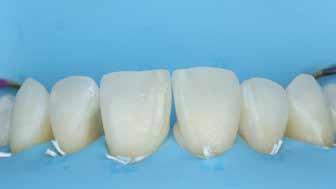

Az alábbi cikkben egy I. osztályú üreg thermo-viszkózus kompozittal, okkluzális matrica technikával történő ellátásának lépéseit ismertetjük (1. ábra). A kofferdám felhelyezését követően az okkluzális felszín anatómiai karakterisztikáját átlátszó, folyékony, fényrekötő kompozit (Clip Flow, VOCO) segítségével rögzítettük. Az anyagot egy bondecset alkalmazásával vittük fel a fog okkluzális felszínére, majd 10 másodpercen keresztül polimerizációs lámpával megvilágítottuk (2–4. ábra). A megkötött átlátszó okkluzális matrica ellenőrzését követően (5. ábra) alkoholba helyeztük (ethanol vagy izopropil-alkohol), az oxigén inhibíciós réteg eltávolítása érdekében. Ezután a szuvas foganyagot eltávolítottuk (6–7. ábra). A zománcot 30 másodpercig, a dentint pedig 15 másodpercig savaztuk (DeTrey Conditioner 36, Dentsply Sirona), majd a felszínt levegő-vízspray segítségével lemostuk (8 –10. ábra). Mivel a fogbélkamrát már csak egy vékony réteg ép dentin fedte, ezért a pulpa vitalitásának megőrzése érdekében az üreg pulpális falait védőréteggel fedtük (DeTrey Conditioner 36, Dentsply Sirona) (11. ábra). Az adhéziót Futurabond DC (VOCO) felhasználásával biztosítottuk. A bondot bondecsettel 20 másodpercen keresztül az üreg falaiba masszíroztuk, majd 5 másodpercen keresztül olajmentes levegő spray-vel megfújtuk a felesleg eltávolítása és a bondréteg elvékonyítása érdekében. A bondot ezt követően 10 másodpercen keresztül polimerizációs lámpával megvilágítottuk (12–13. ábra). Az üreg alját nagyon vékonyan folyékony kompozitréteggel fedtük (GrandioSO Light Flow, A3.5, VOCO), amelyet 20 másodpercen keresztül polimerizációs lámpával megvilágítottuk (14–15. ábra). A bulk-fill tömőanyagot (VisCalor bulk, A2) egy olyan kézi applikátor

2. ábra: A kofferdám felhelyezése. – 3. ábra: A Clip Flow felvitele bondecset segítségével. – 4. ábra: A Clip Flow megvilágítása.